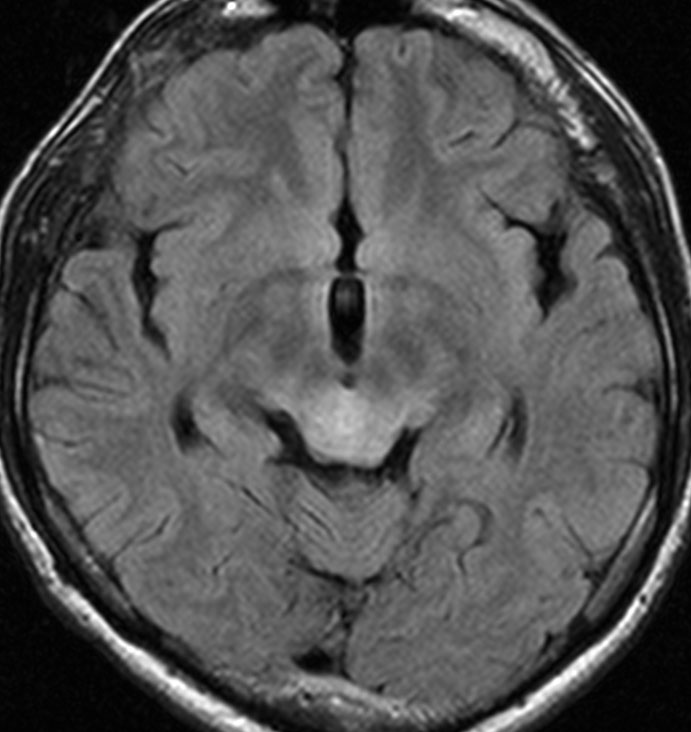

頭部打撲で検査され偶然発見された19歳男性ものです。中脳視蓋全体が腫大して腫瘍化しています。左側にのう胞があり周囲が淡くガドリニウムで増強されます。

中脳水道の癒着閉塞により,高度の停止性水頭症になっています。高身長ですが頭囲が61cmありました。小さい頃から頭が大きいので家族も気にならないようです。数年以上あるいは10年近くの長期にわたってこの水頭症は変わらないのでしょう。

頭痛などの症状はなく,眼底所見も視神経乳頭の異常はありませんでした。無治療で経過観察をしています。認知機能も全く正常で,国立大学から大学院に進む予定です。